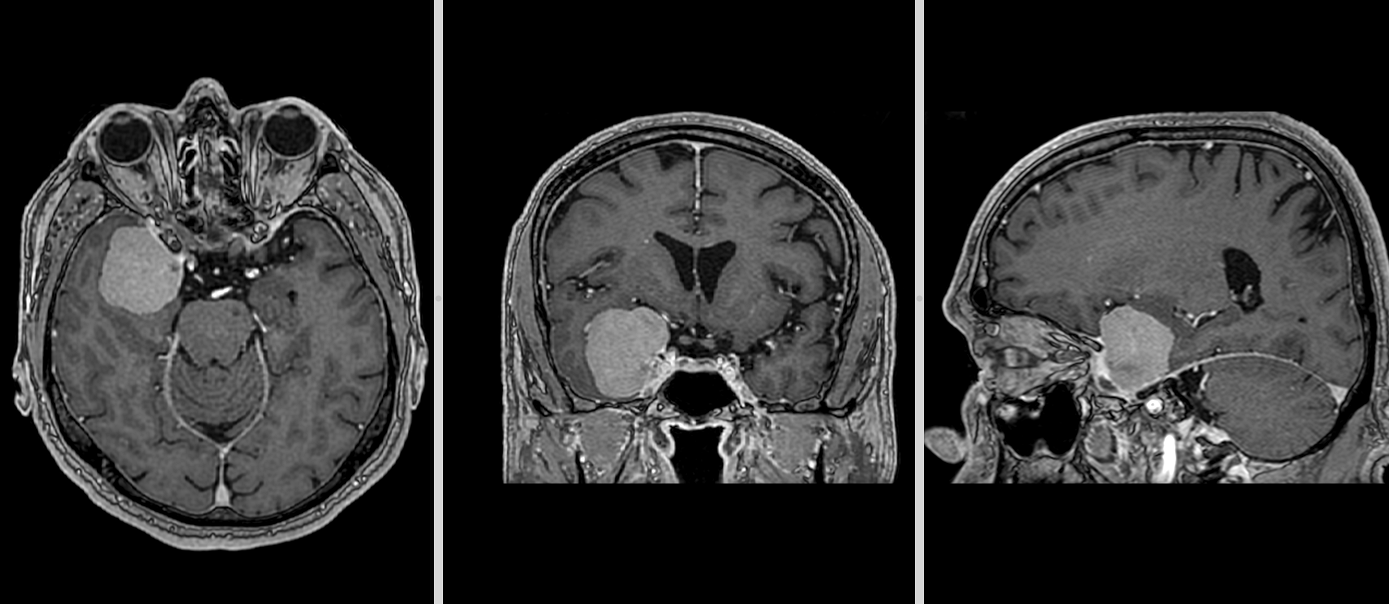

Vă prezentăm cazul unui pacient diagnosticat cu meningiom de aripă de sfenoid dreaptă, o tumoră cerebrală benignă care se dezvoltă...